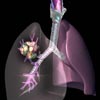

Η αξονική τομογραφία καλύτερη στον εντοπισμό του καρκίνου των πνευμόνων

Ουάσινγκτον: Η εξέταση των πνευμόνων των καπνιστών με αξονική τομογραφία αντί της κοινής ακτινογραφίας επιτρέπει τη μείωση κατά 20% της θνησιμότητας από το καρκίνο των πνευμόνων, σύμφωνα με αμερικανική έρευνα.